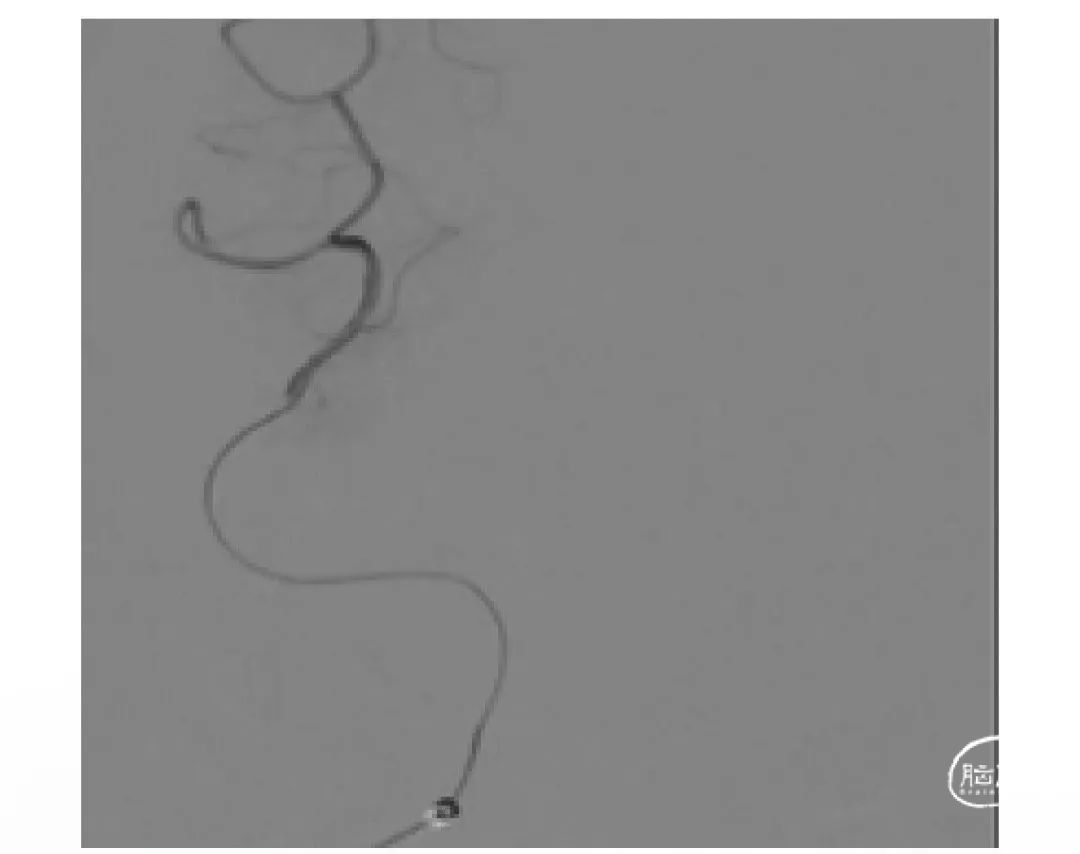

上海心玮医疗科技股份有限公司(股票代码:06609.HK)成立于 2016 年,公司致力于提高创新医疗技术的可及性,守护生命健康。六年时间,心玮医疗在神经介入领域开拓性地打造了国内首个卒中治疗及预防一站式解决方案,拥有从急性缺血性卒中和神经血管狭窄治疗、缺血性卒中预防、出血性卒中治疗到介入通路器械的全产品管线,申请专利超过 100 项,产品年产能超过 15 万件,销售渠道覆盖国内超过 30 个省(含直辖市和自治区)的 1400 多家医院。